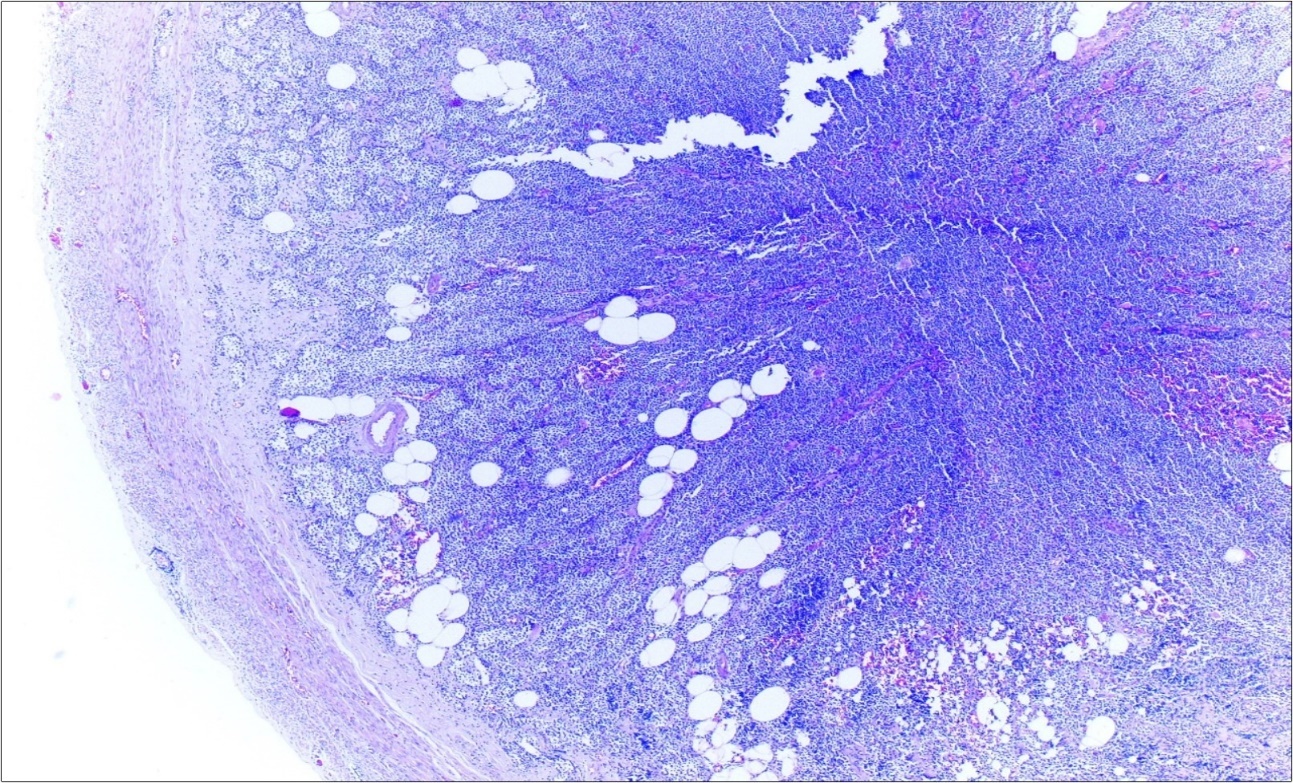

A 63-year-old woman presented to the Department of General Surgery as an outpatient with abdominal pain. Physical examination showed the signs of acute appendicitis and appendectomy was performed. During microscopic examination, a small focus of atypical monotonous lymphoid cell population was seen and the material was sampled totally. The pathological examination revealed MALT lymphoma (Figure 1), with diffuse positivity of cluster of differentiation (CD) 20 (Figure 2), CD 79a and B-cell lymphoma (Bcl- 2) (Figure 3) with just a few CD3 positive lymphoid cells. However, no evidence of adenocarcinoma was found in the appendectomy specimen. After the diagnosis of lymphoma, a complete colonoscopy was planned and this revealed a solid tumoral mass in the caecum measuring 5x4x4 cm. Computed tomography of the abdomen and pelvis revealed mesenteric lymphadenopathy associated with a mass in the caecum with multiple nodules in liver consistent with metastasis (Figure 4). Frozen sections were not obtained since the treatment method would not be affected. The patient underwent anterior resection with regional lymphadenectomy, with the pathological assessment of the resected specimen revealing a collision tumor consisting of a poorly differentiated adenocarcinoma extending through the muscularis propria with MALT lymphoma (Figure 5). Microscopic evaluation of the 11 regional lymph nodes in the mesentery of the resected colon and liver biopsy showed diffuse infiltration of MALT lymphoma with metastasis of adenocarcinoma (Figure 6). According to immunohistochemistry, atypical lymphocytes were positive for CD 20, Bcl-2, and negative for CD3, CD5, CD10, CD23, Bcl-6, terminal deoxynucleotidyl transferase, and cyclin D1. The proliferation fraction (MIB-1 immunostaining) was approximately 20%. The morphological and immunohistochemical findings were used to confirm the diagnosis of synchronous presentation of MALT lymphoma and colon adenocarcinoma within the caecum, mesenteric lymph nodes and liver metastases.

Figure 1.Appendix lumen infiltrated with B lymphoid cells (h&e;x100)